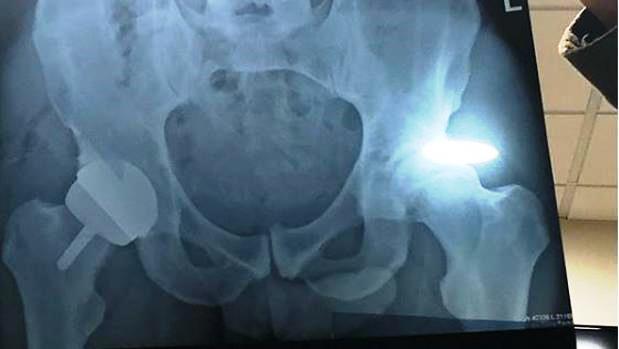

Andy Murray volvió este martes al primer plano de la actualidad al compartir en las redes sociales el resultados de su operación de cadera. El tenista escocés, que se retirará este año, pasó por quirófano en Londres y al término de la intervención quiso compartir con sus seguidores el resultado de la misma.

«Con suerte, este será el final de mi dolor en la cadera. Ahora tengo una cadera de metal», compartió en su cuenta de Instagram junto a dos fotos, una tendido en la camilla, y otra de una radiografía. De lo que no se dio cuenta el escocés es de que en la imagen, además de sus huesos y la prótesis metálica que le habían colocado, también se podía ver con cierta nitidez su pene.

La respuesta de los seguidores del tenista no se hicieron esperar, destacando el detalle que se le había pasado por alto a Andy Murray y con todo tipo de comentarios jocosos.